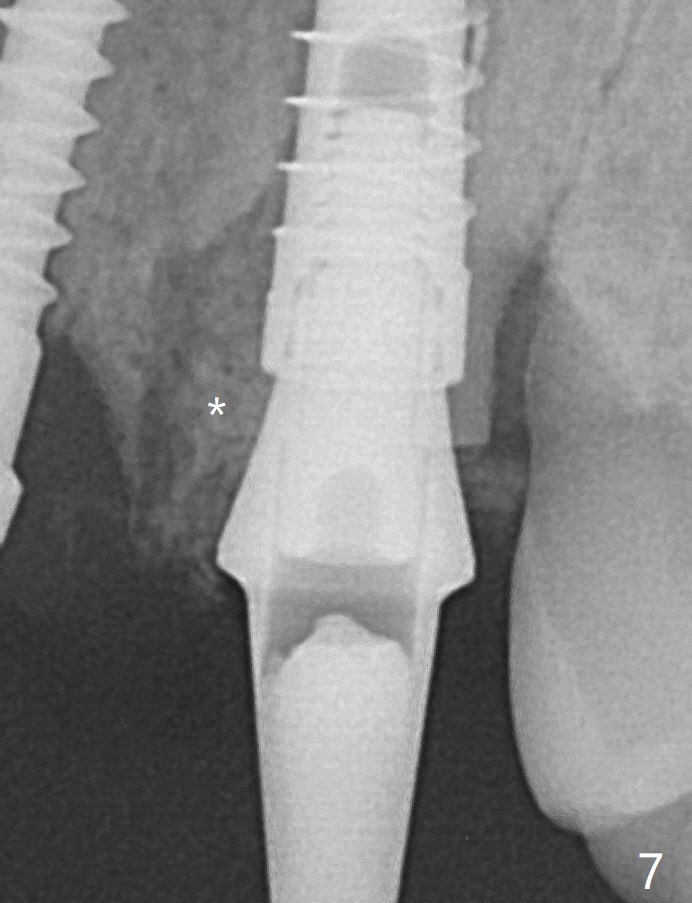

The socket shield at #11 is apparently incomplete, since the apical gutta percha (Fig.2 <) and the apex of the root (Fig.2,3 R) are not removed. The bone is hard when a 1.6 mm drill is being used (Fig.2) as the apical native bone is almost exclusively composed of the cortices. Two of the apical threads of 3.5x13 mm implant are bent, while the implant is placed deeper than the osteotomy (Fig.3,7). After placement of a 4.5x15 degrees A (2mm) angled abutment and Vanilla graft (Fig.7 *), an immediate provisional is fabricated. There is smooth transition from the grafted bone to the native bone 4.5 months postop (Fig.10). Low Magnification, High Magnification of Fig.7,10.